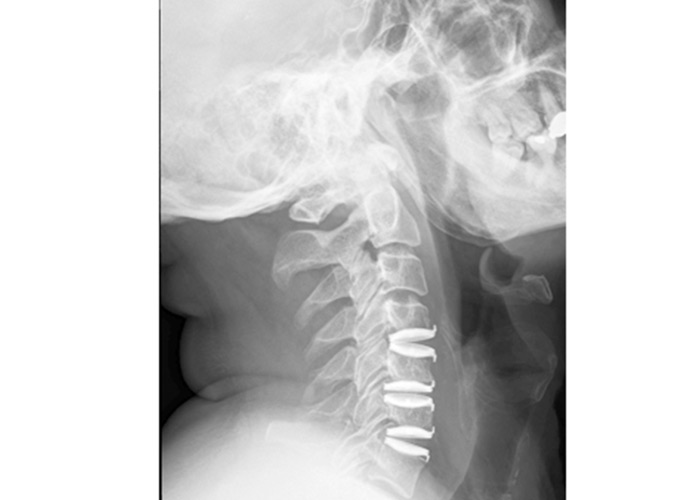

Se comenzó por el nivel C6-C7, se completó discectomía, resección de los osteofitos óseos posteriores y del ligamento vertebral común posterior. Se liberó ambos forámenes C6-C7, bilateralmente, implantándose prótesis de Bryan (Medtronic). Se realizó nuevamente la técnica en los niveles C5-C6 y C4-C5, liberando ambos forámenes y voluminoso osteofito posterior del borde inferior de C5.